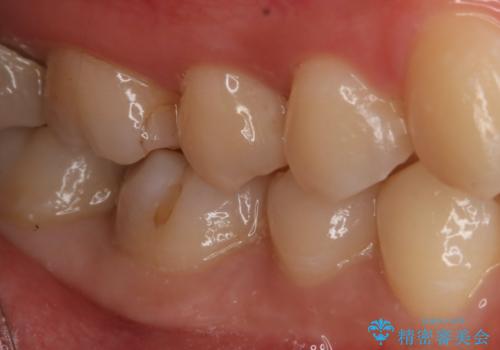

- 右下大臼歯の保険材料劣化に伴う虫歯の治療を希望された患者さまです。

審美性や精度の高い治療を希望されたので切削量や形態を考慮し、セラミックインレーでの治療を選択しました。

保険治療で使用される材料は劣化しやすく直下で虫歯が進行していることが多いです。

今回の患者さまは遠心部の虫歯が深かったのでCRで裏層した上で形成・印象を行いインレーセットを行っています。